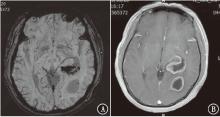

目的探讨磁敏感加权成像(SWI)在颅内转移瘤中的鉴别诊断价值。方法收集2018年 1月至2020年4月新疆维吾尔自治区人民医院住院患者中原发肿瘤为肺癌、乳腺癌、肾癌、直肠癌、膀胱癌、黑色素瘤的颅内转移瘤及胶质母细胞瘤患者63例,半定量评估肿瘤内的敏感性信号强度(ITSS)分级。比较颅内转移瘤与胶质母细胞瘤ITSS分级。结果81个颅内转移瘤中,0级为36个(44.4%),Ⅰ级为25个(30.9%),Ⅱ级为14个(17.3%),Ⅲ级为6个(7.4%);27个胶质母细胞瘤均为Ⅱ~Ⅲ级(100%)。肺癌转移瘤0~Ⅰ级占73.6%(28/38),乳腺癌转移瘤0级占84.6%(22/26),肾癌转移瘤Ⅱ级占5/6,直肠癌转移瘤0~Ⅰ级占4/5,胶质母细胞瘤Ⅲ级占77.8%(21/27)。颅内转移瘤与胶质母细胞瘤ITSS分级组间差异有统计学意义(Z=7.013,P<0.001)。采用受试者工作特征曲线分析显示,ITSS≤Ⅰ级判断颅内转移瘤的敏感性为100%,特异性为75.3%,曲线下面积为0.936(95%CI为0.891~0.980,P<0.001)。结论颅内转移瘤ITSS分级多表现为0~Ⅰ级,胶质母细胞瘤多表现为Ⅱ~Ⅲ级。SWI在颅内转移瘤中有一定的鉴别诊断价值。

ObjectiveTo explore the value of susceptibility weighted imaging (SWI) in differential diagnosis of intracranial metastatic tumors.MethodsSixty-three patients with intracranial metastatic tumors (primary tumors of lung cancer, breast cancer, kidney cancer, rectal cancer, bladder cancer and melanoma) and glioblastomas in People's Hospital of Xinjiang Uygur Autonomous Region from January 2018 to April 2020 were collected, and the intratumoral susceptibility signal intensity (ITSS) was evaluated semi-quantitatively. The grading characteristics of ITSS of metastatic tumors and glioblastomas were compared.ResultsAmong the 81 intracranial metastatic tumors, 36 (44.4%) were grade 0, 25 (30.9%) were grade Ⅰ, 14 (17.3%) were grade Ⅱ and 6 (7.4%) were grade Ⅲ. Among the 27 glioblastomas, 27 (100%) were grade Ⅱ-Ⅲ. Grade 0-Ⅰ metastatic tumors of lung cancer accounted for 73.6% (28/38). Grade 0 metastatic tumors of breast cancer accounted for 84.6% (22/26). Grade Ⅱ metastatic tumor of kidney cancer accounted for 5/6. Grade 0-Ⅰ metastatic tumors of rectal cancer accounted for 4/5. Grade Ⅲ glioblastomas accounted for 77.8% (21/27). The difference of ITSS classification between intracranial metastatic tumors and glioblastomas was statistically significant (Z=7.013,P<0.001). According to the receiver operating characteristic curve analysis, the sensitivity and specificity of ITSS ≤grade Ⅰ were 100% and 75.3% respectively, and the area under the curve was 0.936 (95%CI: 0.891-0.980,P<0.001).ConclusionThe patients with intracranial metastatic tumor usually present ITSS grade 0-Ⅰ, and the patients with glioblastoma usually present ITSS grade Ⅱ-Ⅲ. SWI has a certain value for differential diagnosis of intracranial metastatic tumors.